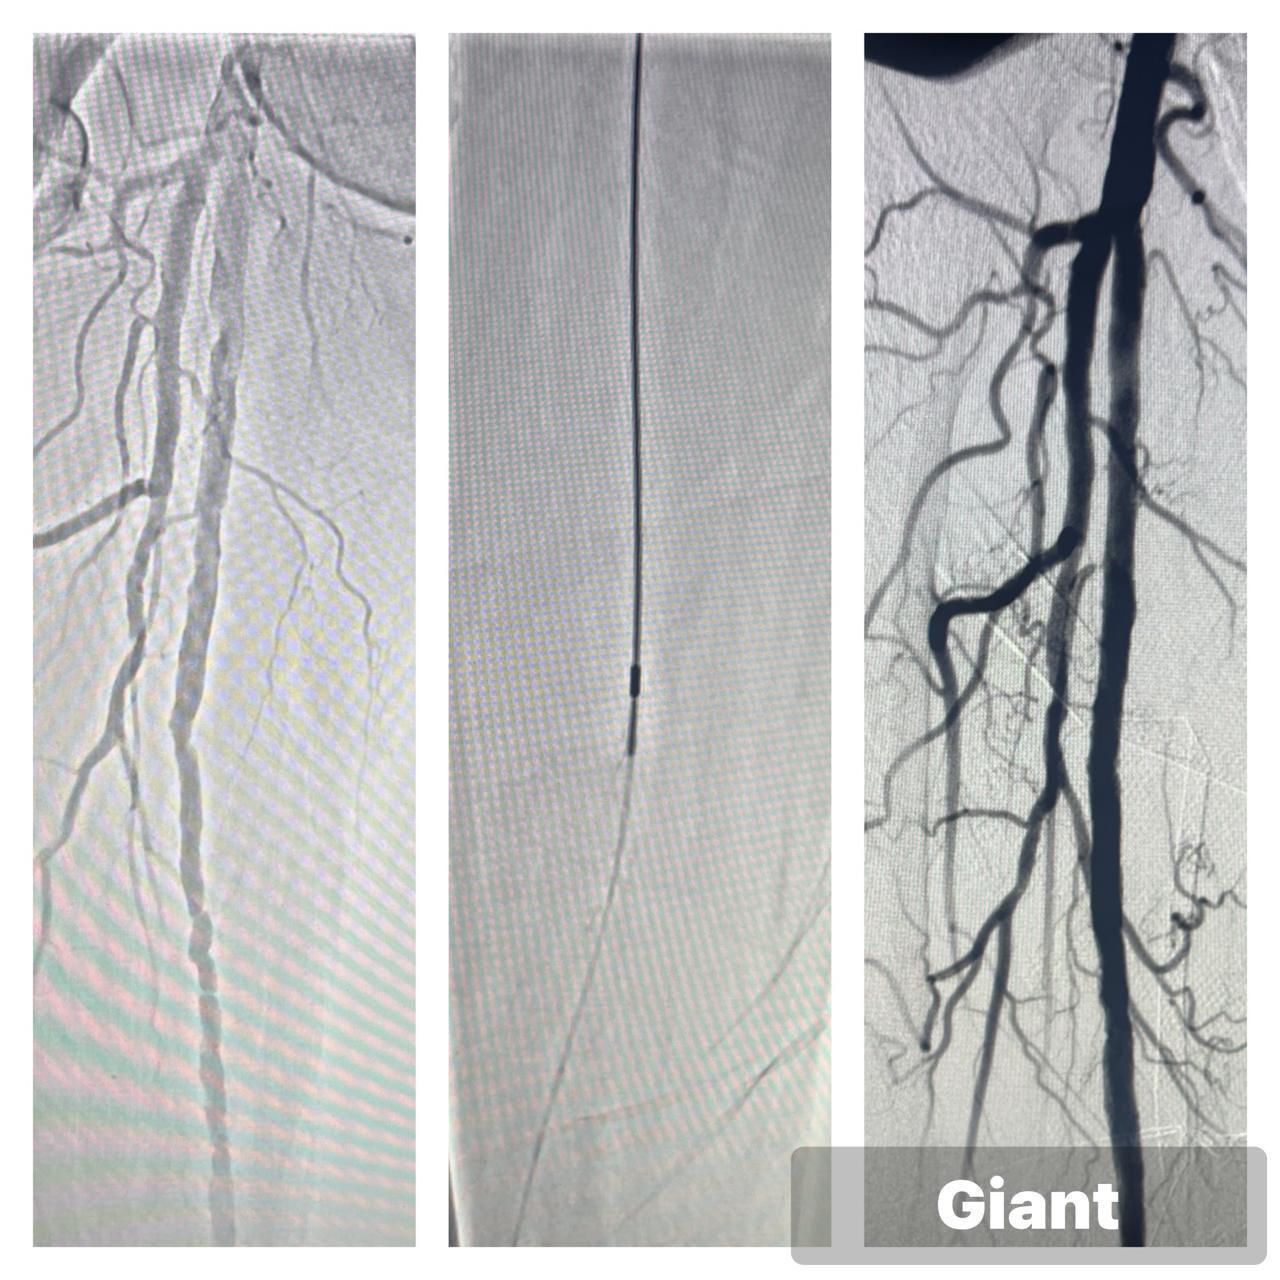

Peripheral Angioplasty procedure at Sarda Vascular Centre Dehradun

Interventional Radiology (IR) uses real-time imaging such as X-ray, ultrasound, CT, or MRI to guide tiny instruments through the body for treatment — without large surgical incisions.